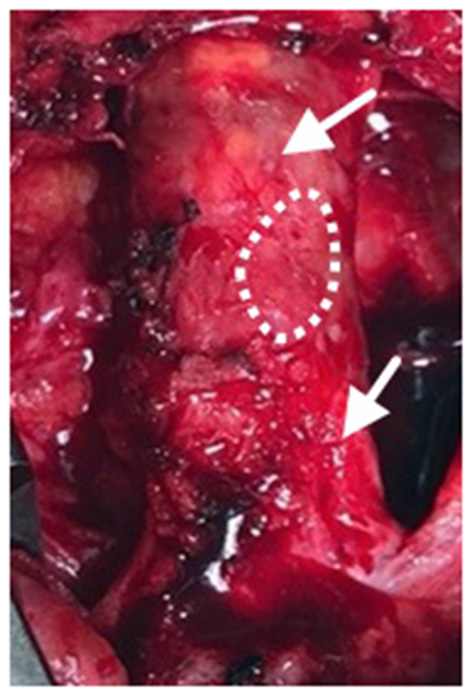

Nineteen months after the initial procedure, the patient again developed disabling symptoms and presented with further progression of distal disease. A month later, a right femoral-to-above-knee popliteal artery bypass was performed using a prosthetic conduit. At the time of this surgery, both previously placed SIS-ECM patches were indistinguishable from the surrounding vascular tissue and could only be identified by the perimeter polypropylene sutures used to implant the patches (Figures 1, 4). Similar to the fate of the first patch used, the second patch was also visually indistinguishable from the rest of the vessel walls. Since this procedure required a longitudinal arteriotomy in the CFA at the level of the initial SIS-ECM patch, a tissue specimen including the anastomosis between the first patch and the previous endarterectomized vessel was removed and sent for evaluation by an independent laboratory. Analysis of the specimen showed the area of the patch to be histologically identical to the adjacent endarterectomized vascular tissue, with no evidence of inflammation or degeneration in any areas of the patch (Figure 5). Post-operatively, the patient had normal non-invasive testing and complete resolution of their lower extremity discomfort.

Figure 4

Following progression of distal disease 20 months after the index procedure, a third operation was performed with creation of a right femoral to above-knee popliteal artery bypass. At this time, the two previous SIS-ECM patches in the common femoral artery appeared to be completely incorporated into the native femoral system (arrows). A specimen, including the anastomosis between the patch and the endarterectomized artery, was removed for histologic evaluation (dashed outline).